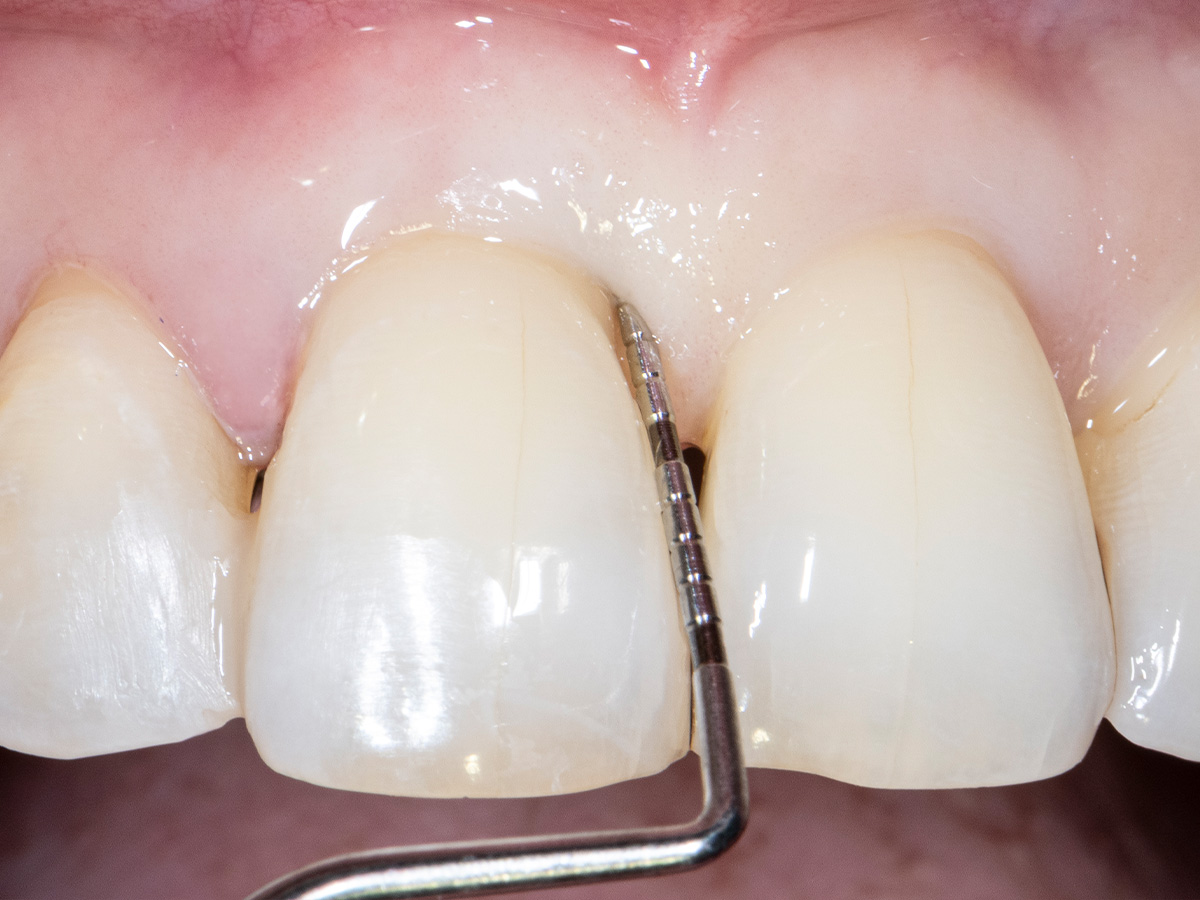

Die klinische Untersuchung nach sechs Monaten zeigt einen parodontal gesunden Zustand, keine Gingivarezession und keine Narbenbildung, da Oberflächeninzisionen auf der bukkalen Seite vollständig vermieden wurden

Abbildung 11

Abbildung 12

Das finale Bild nach Verschluss des Interdentalraumes mittels direkter Kompositrestaurationen zeigt ein ästhetisch ansprechendes Ergebnis.